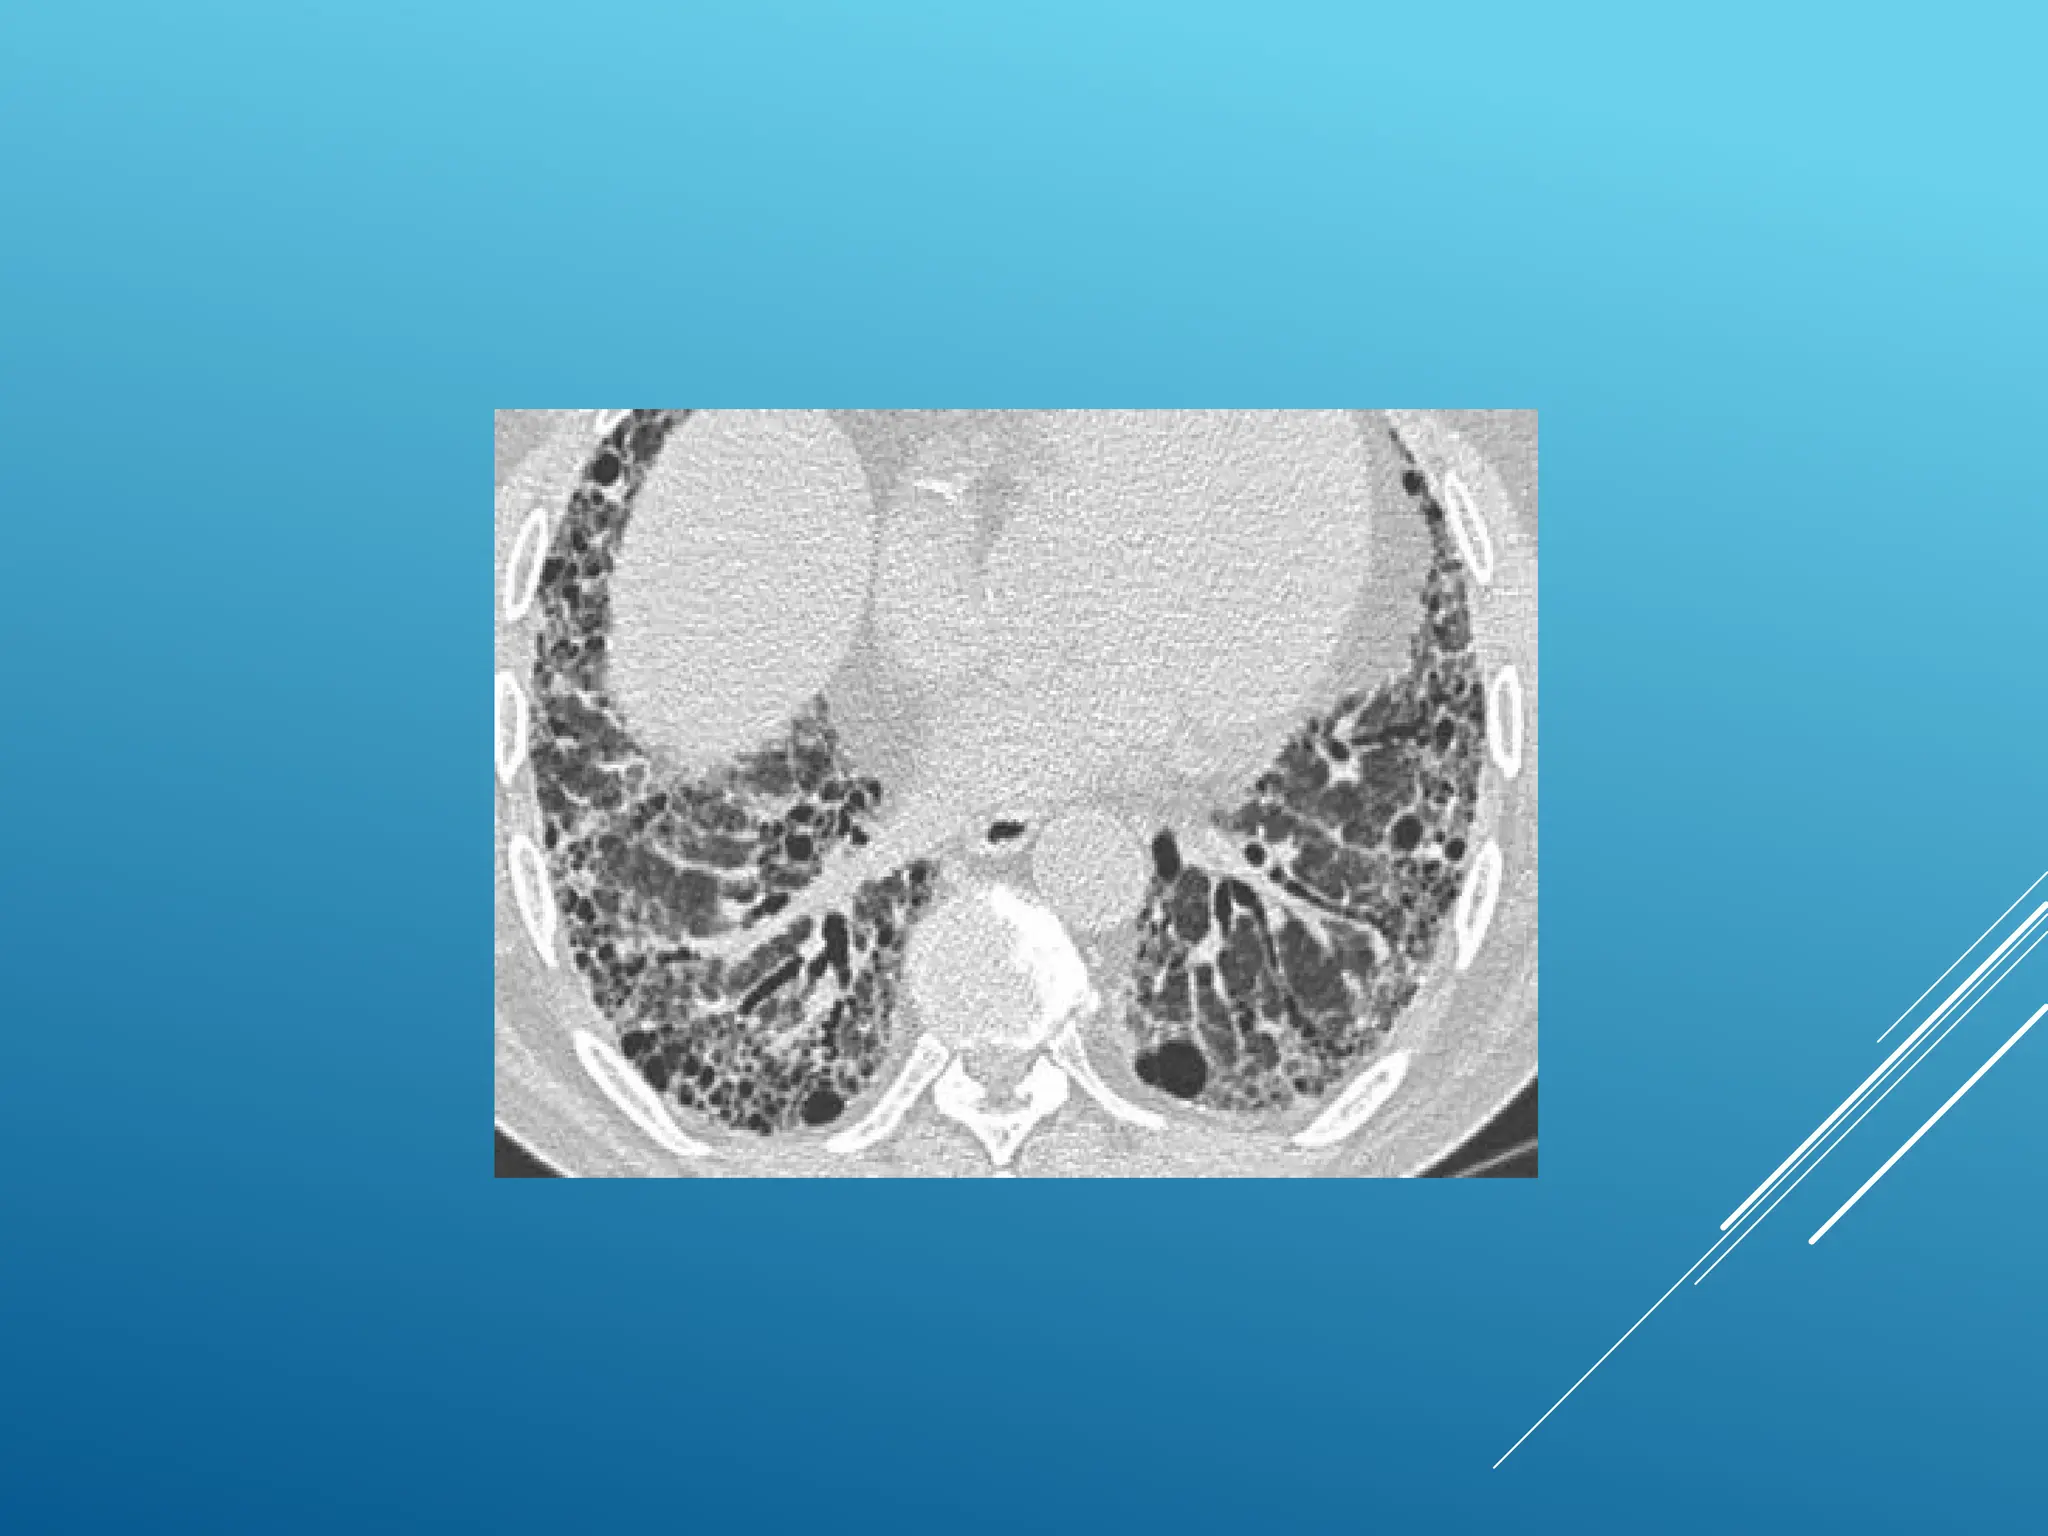

CRAZY PAVING

Combination of ground glass opacity with superimposed

septal thickening

• Alveolar proteinosis

• Sarcoid

• NSIP

• Organizing pneumonia (COP/BOOP)

• Infection (PCP, viral, Mycoplasma, bacterial)

• Neoplasm (Bronchoalveolarca (BAC)

• Pulmonary hemorrhage

• Edema (heart failure, ARDS, AIP)

ALVEOLAR PROTEINOSIS